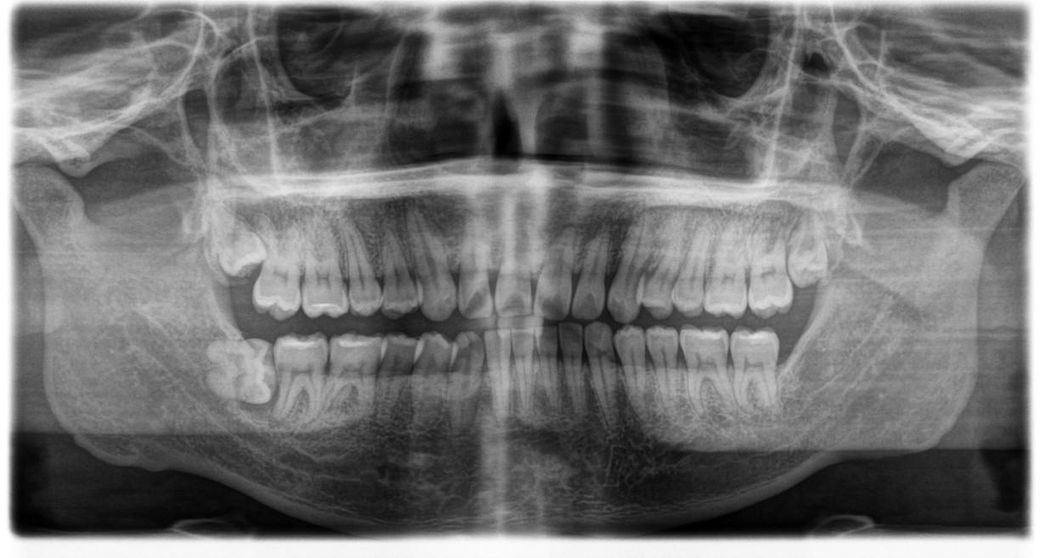

사랑니 발치 후 어금니 치조골 관련해서..

아래 사랑니 어금니 치조골 쪽이 회복이 안될 것 같아서 어금니 상태가 안좋다고 뽑아야할 수도 있다고 하시던데..

어금니쪽에 딱히 통증은 못 느끼긴 했는데 흔들리긴 한다고 하셔서.. 염증은 제가 못느끼긴 했는데 치조골 회복이 아예 안될까요?

사랑니를 발치하고 나면 발치한 부위에는 치조골이 대부분 차오르게 됩니다. 오른쪽 아래에 있는 사랑니의 경우에는 치아 뿌리 끝에까지 치조골이 없는 상태이긴 하지만 우선 감염이 없기 때문에 발치 후 치조골이 차오르는 것을 지켜보는 것이 좋을 것으로 생각됩니다.

사진상으로 왼쪽 아래 사랑니때문에 잇몸뼈가 많이 녹아 잇는 상태 같습니다. 앞치아도 발치를 해야될 가능성도 있어 보입니다.

발치 후 해당 발치 부위의 잇몸뼈가 잘 차오를지 여부는 신체의 재생 능력이 주된 영향을 미치고, 발치 후 처치(염증 조직 제거)에 따라서도 약간 영향을 미칩니다.

일단은 발치 후 옆 치아가 시리거나 불편한 증상이 있는게 아니라면 일단 몇달 지켜보는 것도 방법입니다.

지금으로서는 사랑니 치관 주위로 약간의 낭성 조직이 생기면서 잇몸뼈가 녹았던거 같은데 발치 후 염증조직 잘 긁어냈고, 기다리면 보통은 잇몸뼈가 다시 차오릅니다.